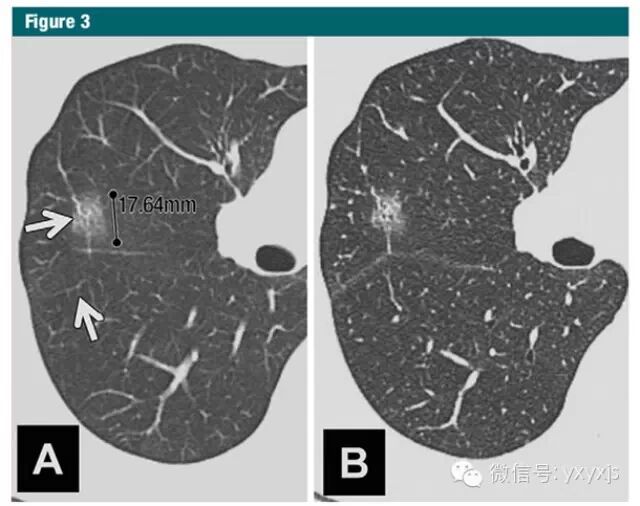

2 孤立的、直径大于5mm的纯GGO,3月后复查,以观察病变是否消失。如持续存在,则每年复查,至少持续3年。

病理上为AAH、原位腺癌和一少部分微浸润腺癌。不建议使用抗生素。PET检查价值不大。CT引导穿刺不推荐,阳性率较低。